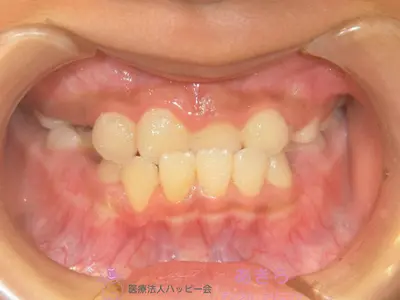

初診時

case-001-5